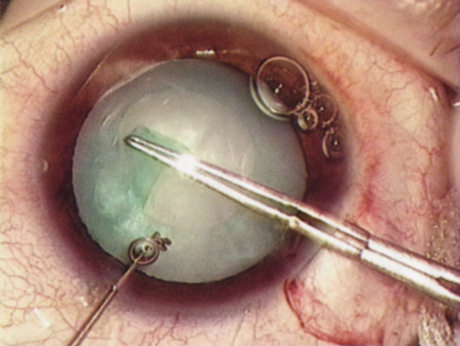

WHITE CATARACT

The introduction of innovative adjunctive devices was able to improve the management of challenging cases. The capsular tension ring introduced independently by Tsutomu Hara37 and Toshiyuki Nagamoto38 in Japan was identified as a major weapon in managing zonular weakness by Ulrich Legler and Bernd Witschel of Germany.39 The CTR came to the United States in 1993,40 after which modifications by Robert Cionni,41 Iqbalk Ahmed and Alan Crandall,42 and Burkhard Dick were developed. Iris reconstruction had been primarily limited to suture techniques developed by Malcolm McCannel43 and later Steven Siepser.44 The prosthetic irides were introduced by German surgeons, Ranier Sundmacher45 and Volker Rasch,46 and brought to the United States by Kenneth Rosenthal and then Robert Osher in 1996.47 Although many devices had been developed to mechanically open the small pupil, it was the stretch technique developed by Luther Fry that greatly simplified these difficult cases.48 Improving visibility by staining the anterior capsule of the white cataract was introduced by Masayuki Horiguchi from Japan (ICG)49 and Gerritt RJ Melles from The Netherlands (Trypan Blue).50